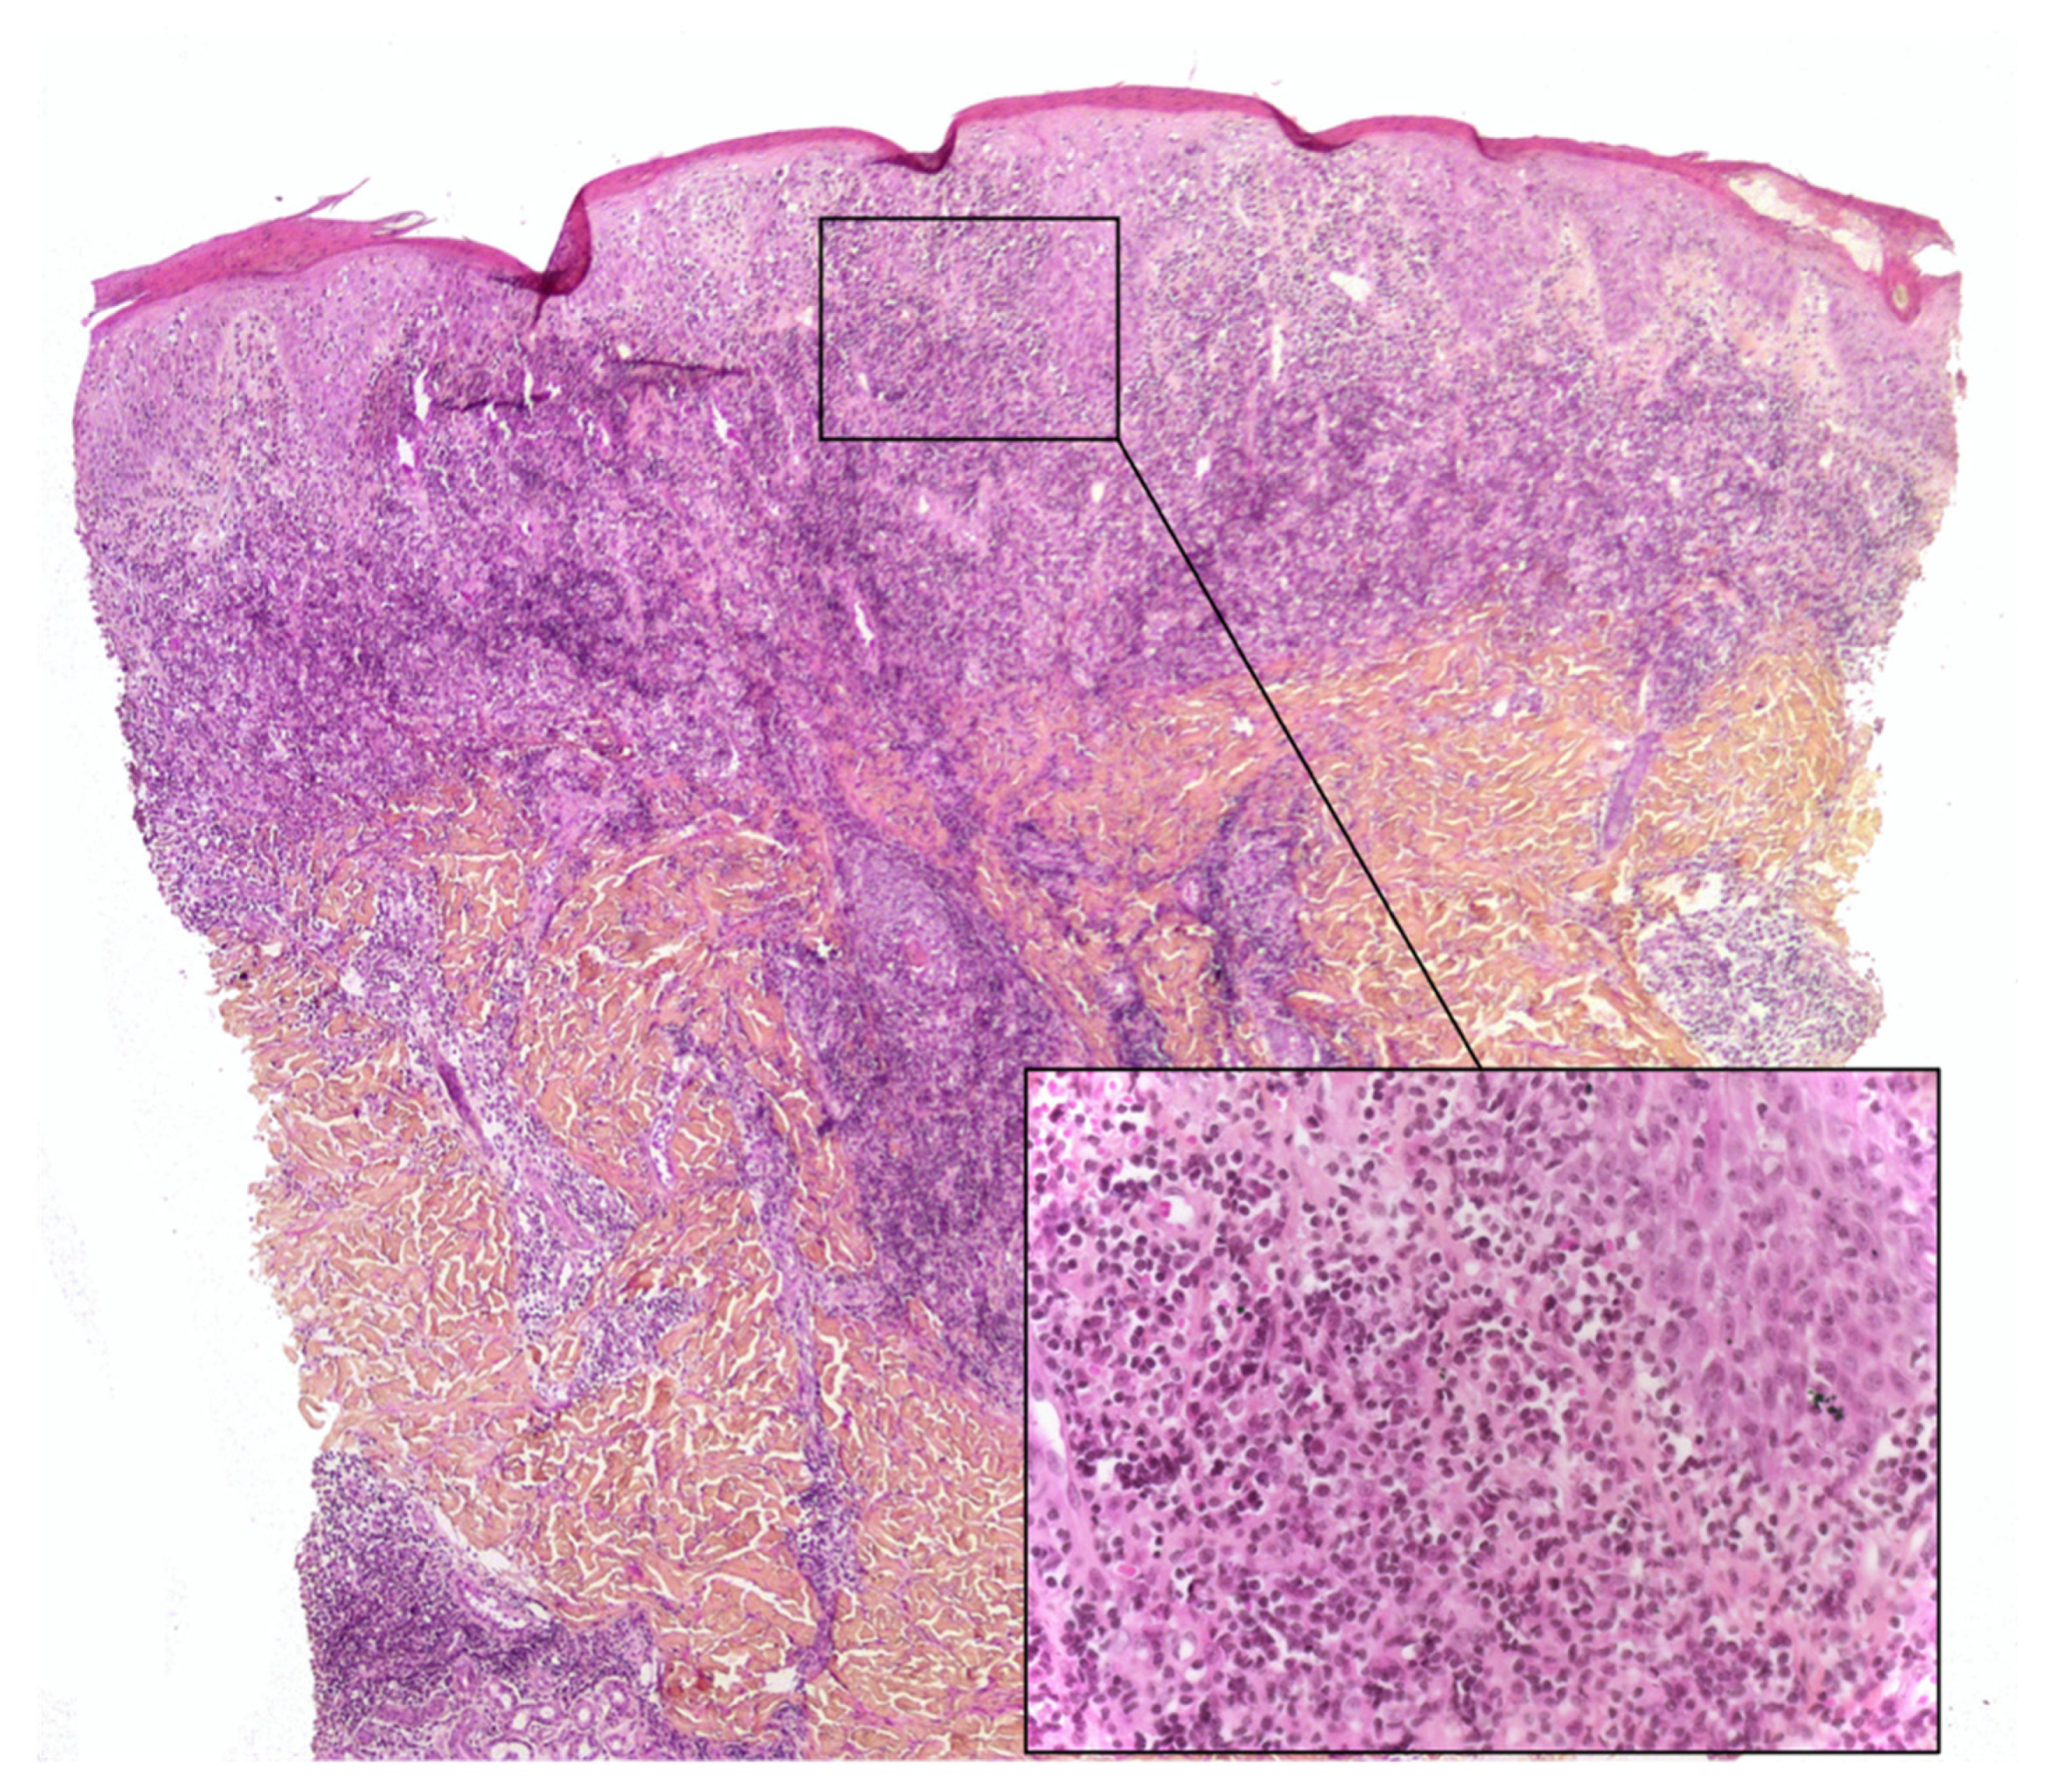

2.3. Pityriasis Lichenoides